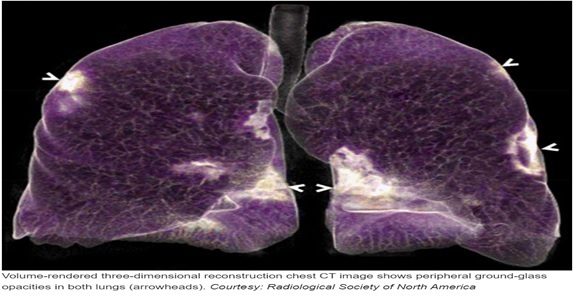

As the accuracy of any machine learning algorithm depends on the type and quality of data that is provided to it, the database for our experiment was very carefully selected. Only those patients(images) were selected whose lung CT scan images showed typical patches on the outer edges of the lungs. first the CT scan images of positive covid and normal healthy person are taken and stored in the computer. Then we are doing some pre-processing steps to enhance the image. We are making separate folders for positive cases and normal cases. For feature extraction and learning of the system, we are using custom vision software based on deep learning algorithm of Microsoft azure. Once the system gets trained, we test the system on the unseen images of positive and normal cases. After getting the results of testing, we check it with the actual condition (positive/normal) of the patient for getting accuracy of the trained model. Next step is to deploy the model,